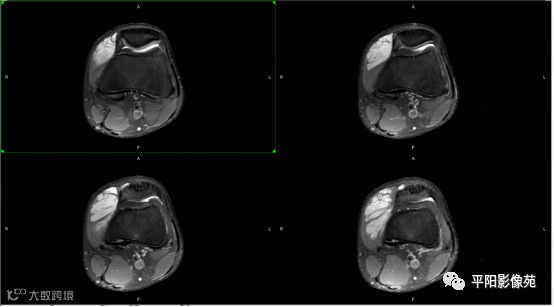

影像表现:

左膝关节股内侧肌内见多房样短T1长T2信号,内可见分隔,增强扫描明显强化,分隔未见明显强化,病灶局部与股骨远端分界不清。

MRI表现:好发于下肢, 较大病灶多为与肢体长轴一致的梭形, 边缘不清, 较小病灶呈类圆形, 边缘较清;②T1WI呈等或稍高信号, 病灶内部或边缘可见线条状或花边状高信号灶, 类似于皮下脂肪信号, T2WI上为明显高信号, 为本病特征性MRI表现;③病灶内静脉石及血管流空影为又一特征MRI表现;④GD-DTPA增强, 病灶明显强化, 其内低信号间隔无强化;⑤可见骨外形改变, 骨质增生及骨质吸收等表现。